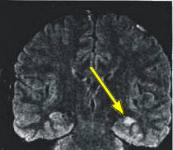

Fig.1 Fig.2 Fig.3

MRI FINDINGS: MRI detects mesial temporal sclerosis by demonstrating size asymmetry and abnormal signal within the atrophied hippocampus. Thin-section, high-resolution oblique coronal MR images are best for detecting these abnormalities, which can be subtle. Heavily T1-weighted images (Fig. 1) are best for detecting size asymmetry of the hippocampal gyri, while T2-weighted images (Fig. 3) and particularly FLAIR (fluid attenuated inversion recovery) images are most sensitive for detecting signal abnormalities (Fig. 2). The above images demonstrate left hippocampal atrophy and mesial temporal sclerosis (arrows).